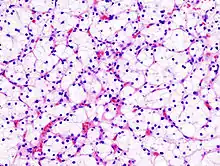

| Micrograph of the most common type of renal cell carcer (clear cell)—on right of the image; non-tumour kidney is on the left of the image. Nephrectomy specimen. H&E stain | |

Histopathology

The gross and microscopic appearance of renal cell carcinomas is highly variable. The renal cell carcinoma may present reddened areas where blood vessels have bled, and cysts containing watery fluids.[58] The body of the tumour shows large blood vessels that have walls composed of cancerous cells. Gross examination often shows a yellowish, multilobulated tumor in the renal cortex, which frequently contains zones of necrosis, haemorrhage and scarring. In a microscopic context, there are four major histologic subtypes of renal cell cancer: clear cell (conventional RCC, 75%), papillary (15%), chromophobic (5%), and collecting duct (2%). Sarcomatoid changes (morphology and patterns of IHC that mimic sarcoma, spindle cells) can be observed within any RCC subtype and are associated with more aggressive clinical course and worse prognosis. Under light microscopy, these tumour cells can exhibit papillae, tubules or nests, and are quite large, atypical, and polygonal.

Recent studies have brought attention to the close association of the type of cancerous cells to the aggressiveness of the condition. Some studies suggest that these cancerous cells accumulate glycogen and lipids, their cytoplasm appear "clear", the nuclei remain in the middle of the cells, and the cellular membrane is evident.[59] Some cells may be smaller, with eosinophilic cytoplasm, resembling normal tubular cells. The stroma is reduced, but well vascularised. The tumour compresses the surrounding parenchyma, producing a pseudocapsule.[60]

The most common cell type exhibited by renal cell carcinoma is the clear cell, which is named by the dissolving of the cells' high lipid content in the cytoplasm. The clear cells are thought to be the least likely to spread and usually respond more favourably to treatment. However, most of the tumours contain a mixture of cells. The most aggressive stage of renal cancer is believed to be the one in which the tumour is mixed, containing both clear and granular cells.[61]